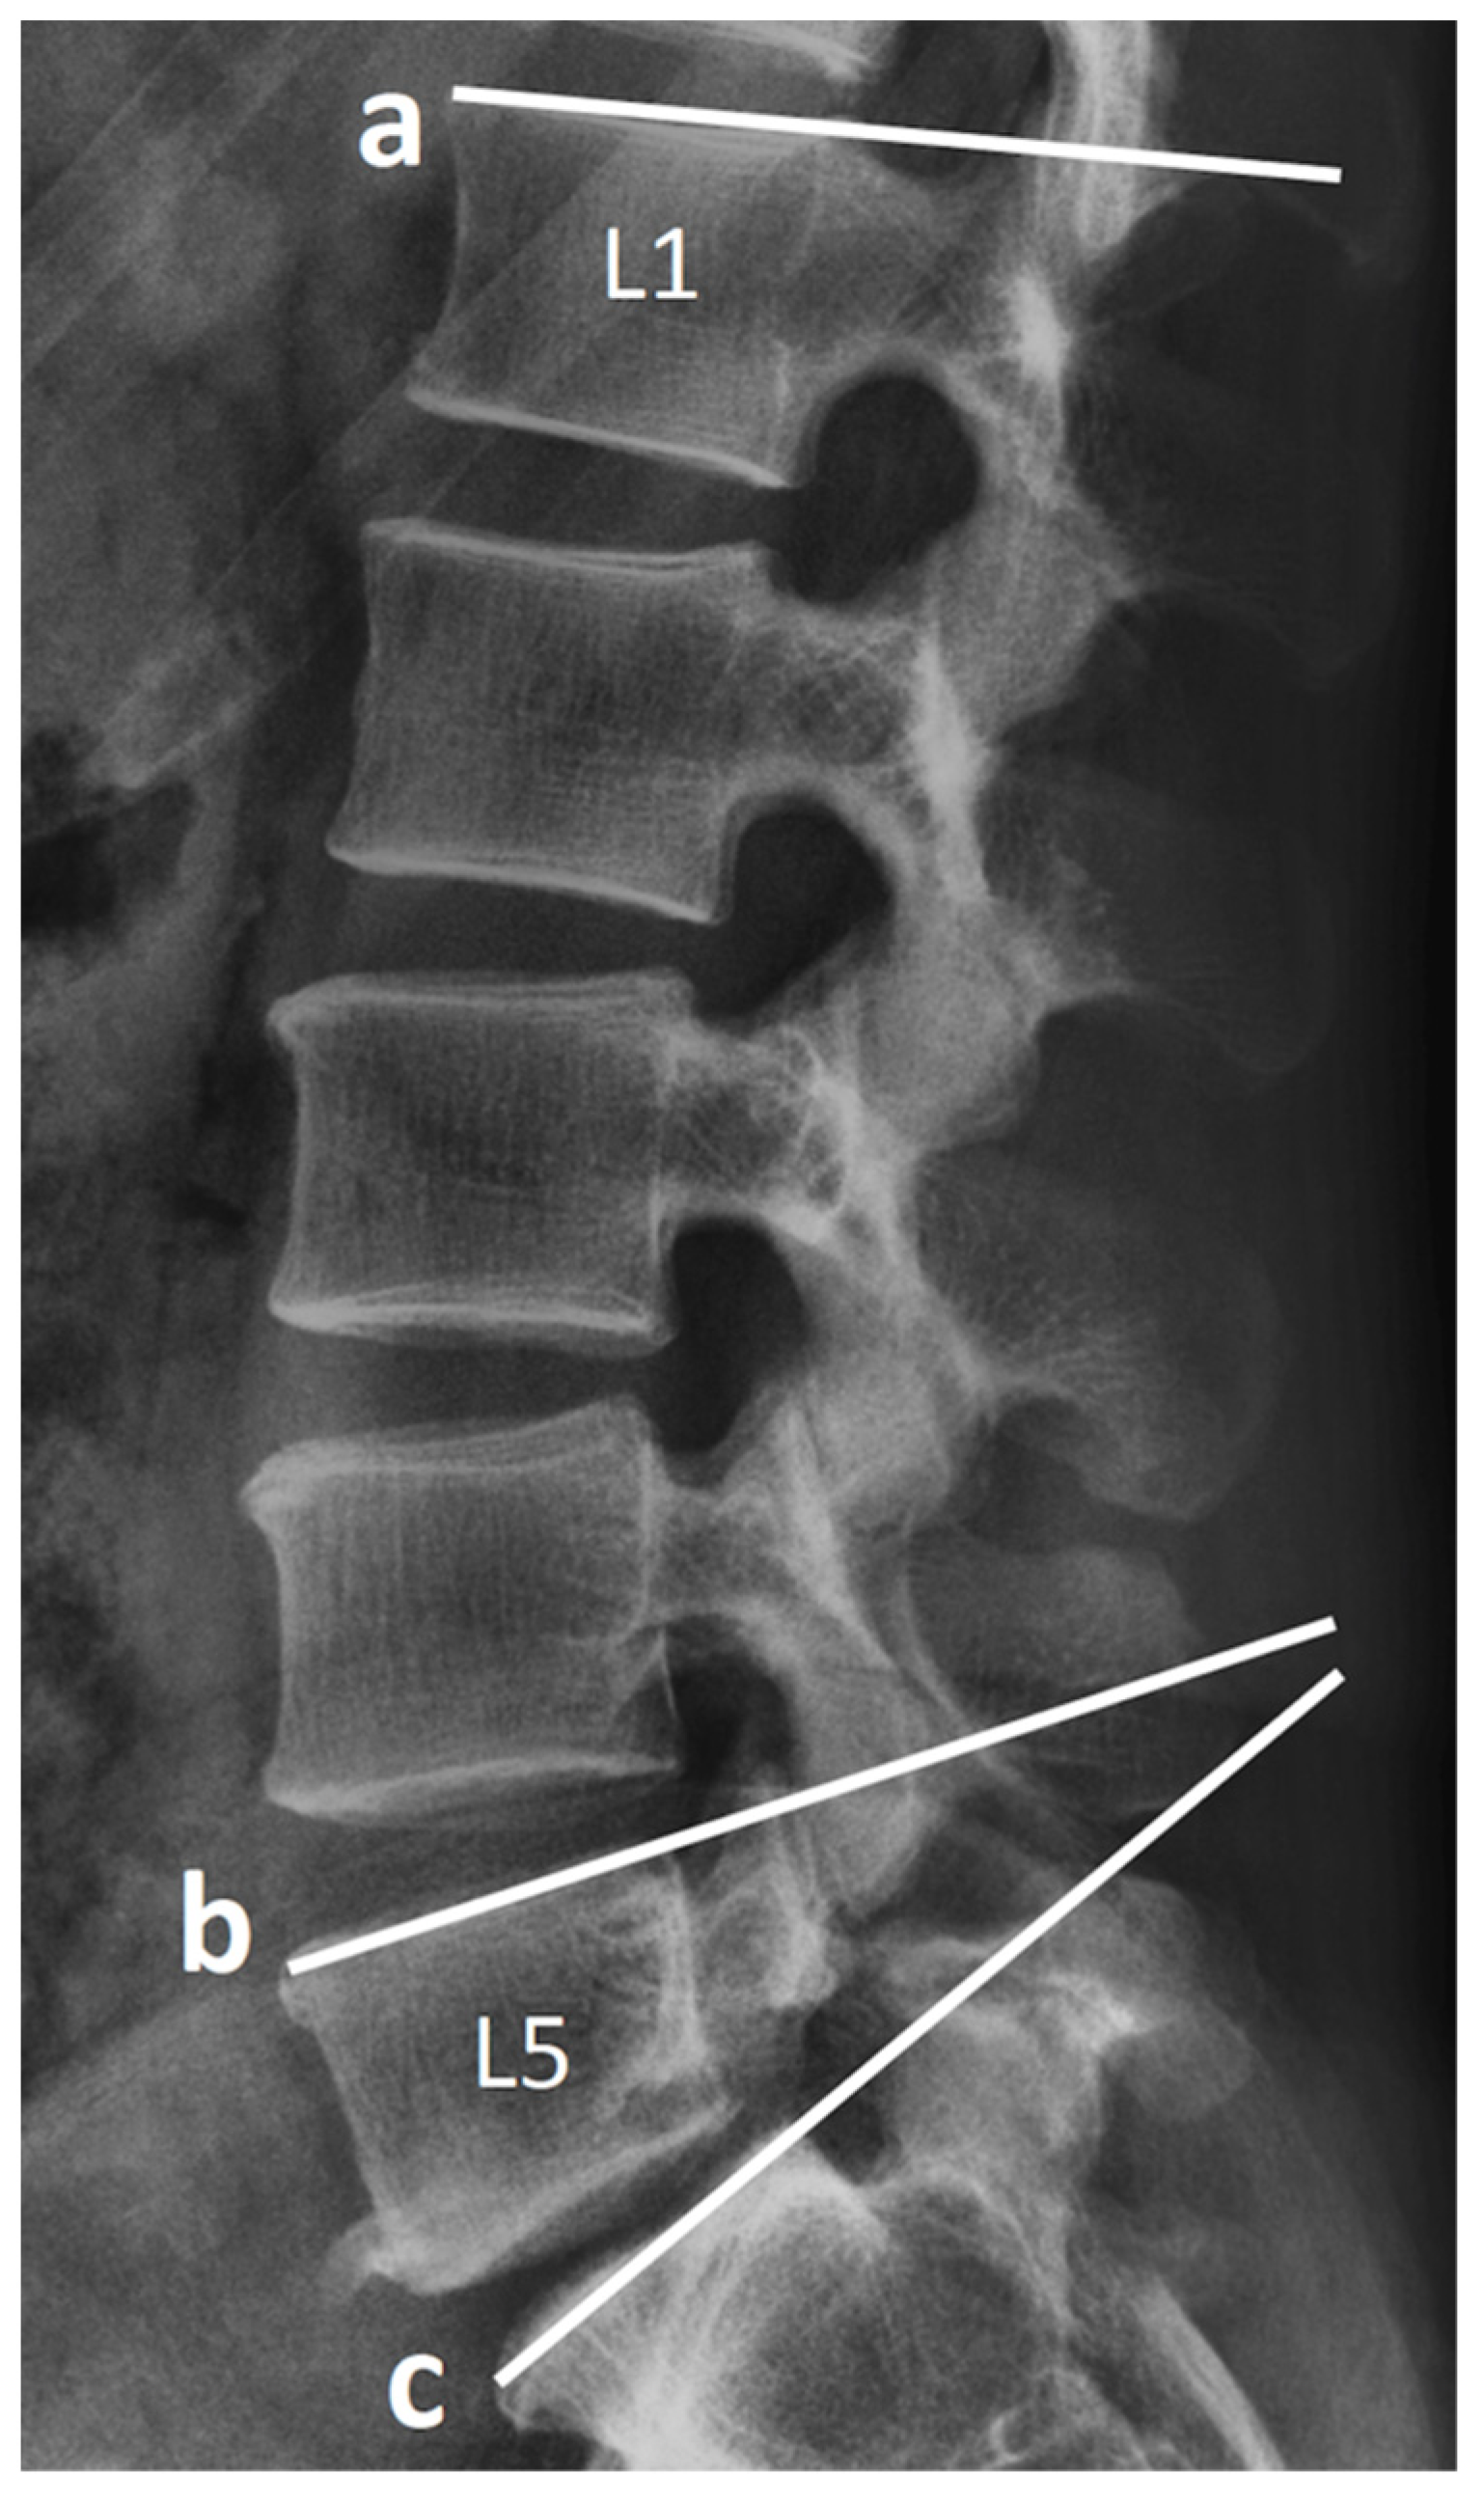

2.3. Radiological Assessment and Clinical Record

| Postop LL (°) | 45.47 ± 13.78 | 33.17 ± 12.52 | <0.001 |

| Postop SL (°) | 20.20 ± 13.54 | 16.71 ± 6.35 | 0.16 |